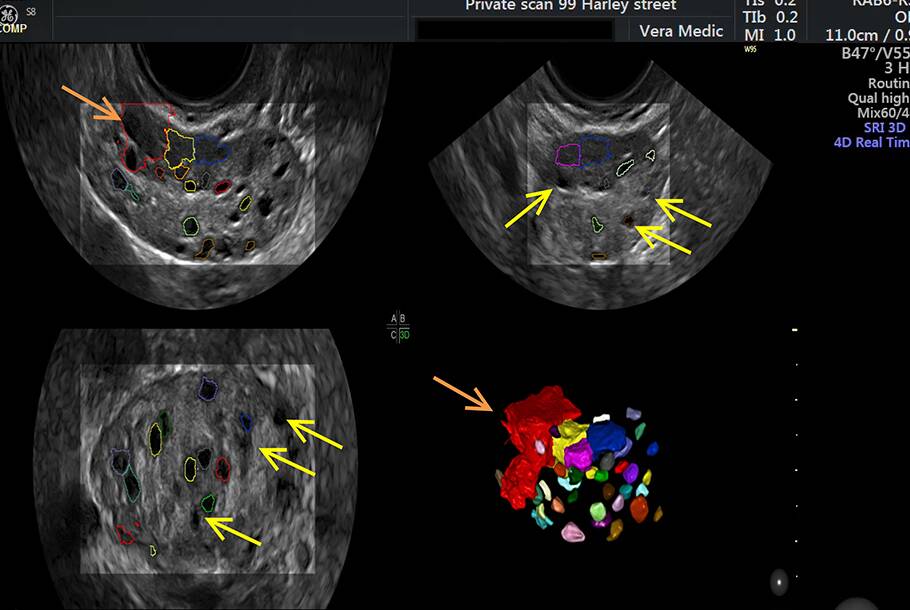

From www.privateultrasoundscanslondon.com

Ovarian Egg Assessment Private Ultrasound Scans London Can Eggs Be Damaged In Ovaries Proper diagnosis and management of these conditions are essential for optimizing fertility. Potential risks associated with egg retrieval. Ovaries, where oocytes are born, harbor. After the hormone treatment has stimulated the ovaries to produce more eggs, those eggs must be retrieved. The number and quality of. When this happens, the ovaries don't make the typical amounts of the hormone estrogen. Can Eggs Be Damaged In Ovaries.